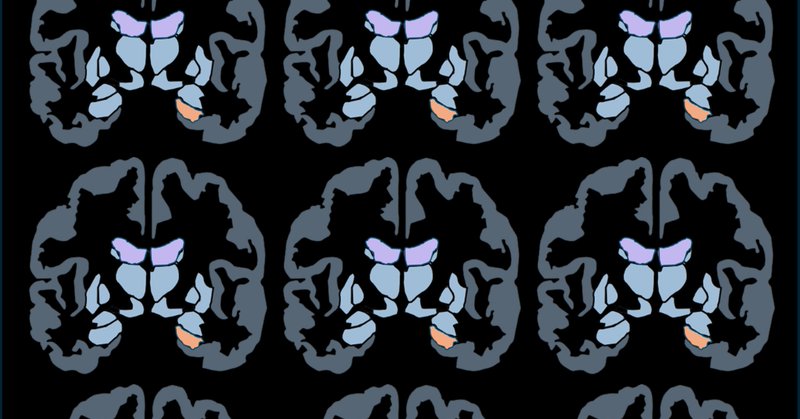

After 5 years of data collection (179 first-time mothers + controls), and 2 years of data analyses and article writing, the first @BeMotherProject paper is out! We uncovered a U-shaped trajectory in maternal GM volume, resolving a long-standing puzzle in the maternal brain field.

Can’t believe our new @NatureComms paper is out! ✨🧠🤰 We tracked a cohort of 179 women before, during, and post-pregnancy, revealing a U-shaped trajectory in the mother’s brain structure linked to steroid hormone fluctuations and maternal attachment. #ParentalBrain 🧵👇